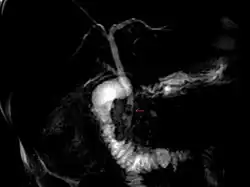

| Magnetic resonance cholangiopancreatography (MRCP) image of two gallstones in the distal common bile duct | |

The diagnosis of choledocholithiasis is suggested when the liver function blood test shows an elevation in bilirubin and serum transaminases. Other indicators include raised indicators of ampulla of vater (pancreatic duct obstruction) such as lipases and amylases. In prolonged cases the international normalized ratio (INR) may change due to a decrease in vitamin K absorption. (It is the decreased bile flow which reduces fat breakdown and therefore absorption of fat soluble vitamins). The diagnosis is confirmed with either a magnetic resonance cholangiopancreatography (MRCP), an endoscopic retrograde cholangiopancreatography (ERCP), or an intraoperative cholangiogram. If the patient must have the gallbladder removed for gallstones, the surgeon may choose to proceed with the surgery, and obtain a cholangiogram during the surgery. If the cholangiogram shows a stone in the bile duct, the surgeon may attempt to treat the problem by flushing the stone into the intestine or retrieve the stone back through the cystic duct.

On a different pathway, the physician may choose to proceed with ERCP before surgery. The benefit of ERCP is that it can be utilized not just to diagnose, but also to treat the problem. During ERCP the endoscopist may surgically widen the opening into the bile duct and remove the stone through that opening. ERCP, however, is an invasive procedure and has its own potential complications. Thus, if the suspicion is low, the physician may choose to confirm the diagnosis with MRCP, a non-invasive imaging technique, before proceeding with ERCP or surgery.